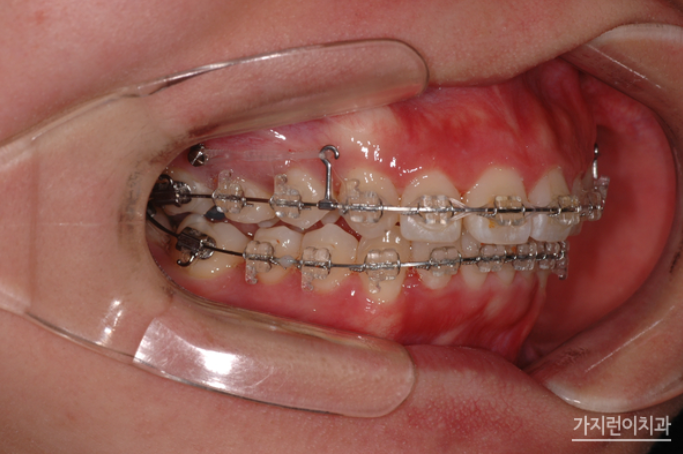

위 환자의 경우 상악 돌출입 증상과 더불어 심한 충치로 인해 발치가 불가피한 악조건을 갖고 있었는데요. 충치는 정도가 심하면 결국 발치를 하게 되고 인공치아를 식립해야 하는 과정을 밟게 되는데요. 그런데 환자의 경우 불규칙적인 치열의 재배열과 더불어 콤플렉스로 자리잡은 돌출입도 교정으로 진행해볼 수 있었습니다. Modified Bonded Cantilever Spring (MBC spring) 교정으로 사랑니에 직접 부착해 사랑니를 세우는 교정을 진행하게 되었는데요. 사랑니가 쓰러져 있는 상태라면 기존의 교정장치를 부착하기 어렵기 때문에 개발된 장치를 사용하고 있습니다. 그러면 장치를 착용한 후의 경과를 볼까요?

하지만 사랑니를 세우는 교정이라고 해서 모든 사람이 Modified Bonded Cantilever Spring (MBC spring) 교정을 사용하지는 않는데요. 환자분의 경우 하악 어금니 발치 공간을 메우는 과정에서 사랑니가 쓰러져 있긴 했지만 교정장치를 부착할 수 있는 상황이었기 때문에 추가적으로 Modified Bonded Cantilever Spring (MBC spring)을 사용하지는 않았습니다. 대신 돌출입 해결을 위해 상악을 후방으로 이동하기 위해 교정용 스크류를 이용해 진행하게 되었는데요. 총 2년 3개월의 치료기간이 소요된 환자분의 교정전후 사진을 확인해볼까요?